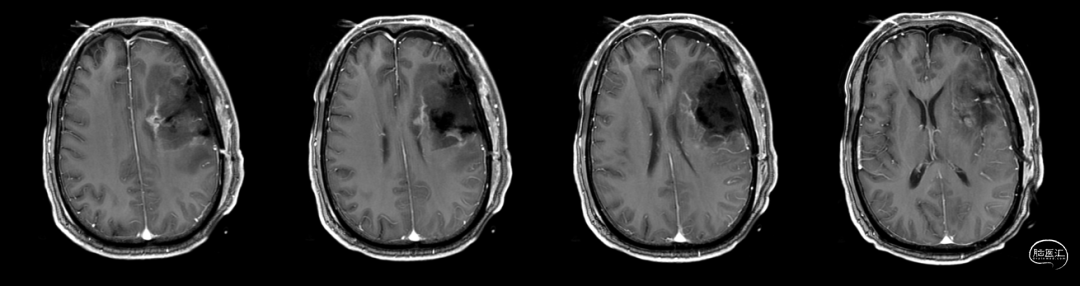

术后48小时MR,可见左额不规则混杂信号影,周围水肿:图示。

术后48小时MR,增强后边缘不规则线样强化,靠近放射冠及侧脑室壁可疑少许残存:图示。

入院前头MRI(2020-3):左侧额岛叶肿块,信号不均匀,其内可见出血和坏死,占位效应明显,周围见水肿。考虑左额岛叶肿瘤(高级别脑胶质瘤可能性大)。于2020年4月行左额岛叶占位性病变切除术。术中见肿瘤组织位于左侧额中回及额下回后部,大小约4m×5cm×5cm,呈烂鱼肉样,色灰红,质软,部分坏死,血运中等,边界不清,侵犯左侧岛叶向下挤压颞叶。显微镜下沿肿瘤周边胶质增生带完整切除肿瘤。术后48小时内复查头MRI平扫、加强,影像显示术腔边缘不规则线样强化,靠近放射冠及侧脑室壁强化明显,可疑少许残存。